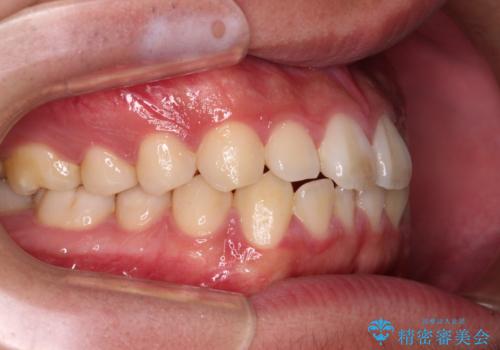

- 上下前歯の叢生を気にして来院された患者様です。

費用を抑え、期間もあまりかけずに治療をしたいとのことで、インビザライン・ライトを用いて矯正治療を行うこととしました。

インビザライン・ライトは、製作できるアライナーの枚数に制限があるため、移動可能な量に限りがあります。

一方で、半年から1年程度で治療を終えることができるため、軽度の歯列不正の患者様には大変お勧めです。